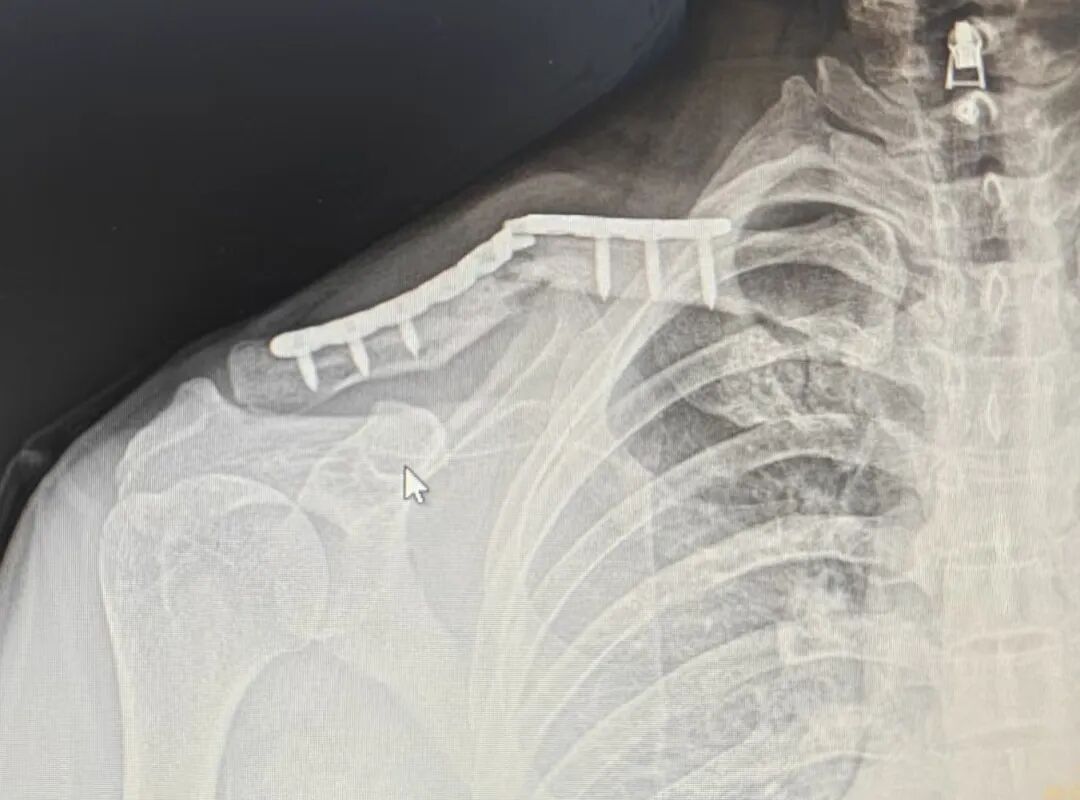

术后第五个月

钢板断裂

骨折也没有愈合

钢板断裂原因?

回头看**次手术

钢板和骨折复位都挺好啊

怎么就断了